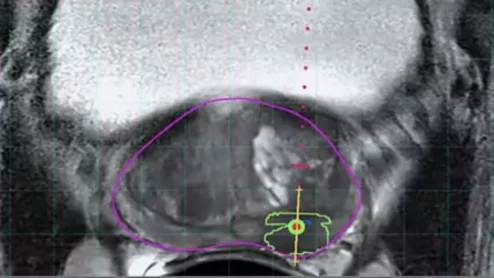

Philips UroNav system gains FDA clearance

The fusion technology integrates pre-procedural MR images of the prostate with intraprocedural ultrasound images in real-time.